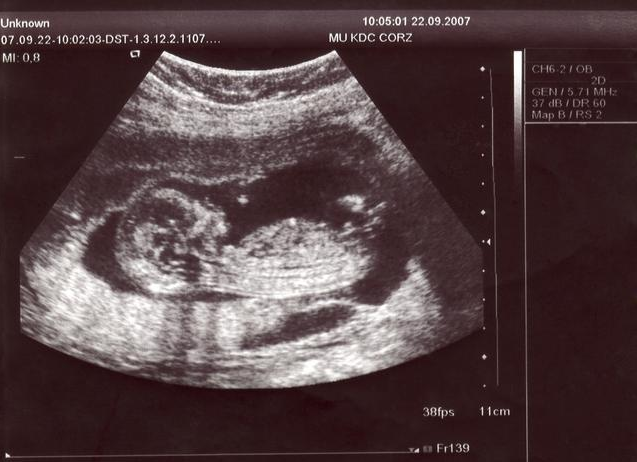

四維彩超是一種先進(jìn)的醫(yī)學(xué)成像技術(shù),能夠在孕期實(shí)時(shí)觀察胎兒的發(fā)育情況,與傳統(tǒng)的二維、三維彩超相比,四維彩超能夠提供更清晰、更立體的圖像,讓準(zhǔn)父母更直觀地了解胎兒的成長(zhǎng)過(guò)程。

胎兒的性別由性染色體決定,男性擁有一個(gè)X染色體和一個(gè)Y染色體,而女性則擁有兩個(gè)X染色體,在孕期,通過(guò)四維彩超可以觀察到胎兒的生殖器官,從而判斷胎兒的性別。

1、選擇合適的時(shí)間:在孕期20周以上進(jìn)行四維彩超檢查較為適宜,此時(shí)胎兒的生殖器官已發(fā)育到一定階段,圖像較為清晰。

2、觀察圖像:在四維彩超圖像上,男性胎兒的生殖器官呈現(xiàn)為細(xì)小的小雞冠狀結(jié)構(gòu),而女性胎兒的生殖器官則呈現(xiàn)為較為平滑的橢圓形結(jié)構(gòu),通過(guò)觀察這些特征,可以初步判斷胎兒的性別。

3、識(shí)別誤區(qū):在觀察四維彩超圖像時(shí),需要注意避免受到其他身體部位(如臍帶、胎盤(pán)等)的干擾,胎兒的體位也會(huì)影響觀察結(jié)果,因此可能需要多次檢查才能確定。

(此處可插入一系列四維彩超圖像,展示男性胎兒和女性胎兒生殖器官的不同特征)